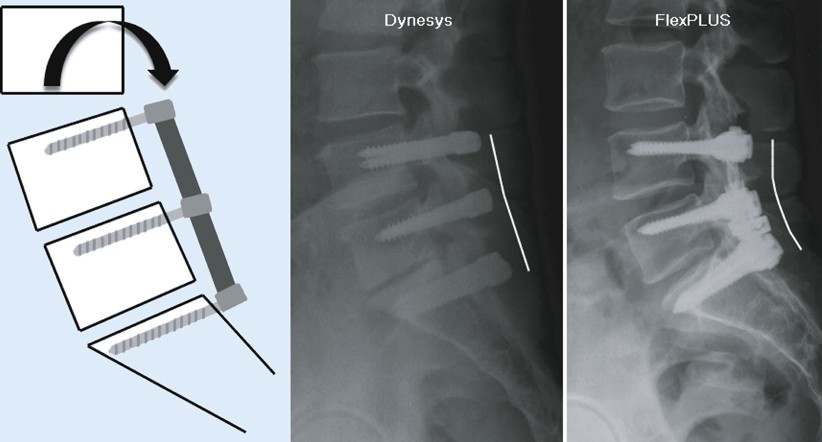

Dynamische Stabilisierung : Spinalkanalstenose, foramenstenose, degenerierte bandscheibe mit und ohne.